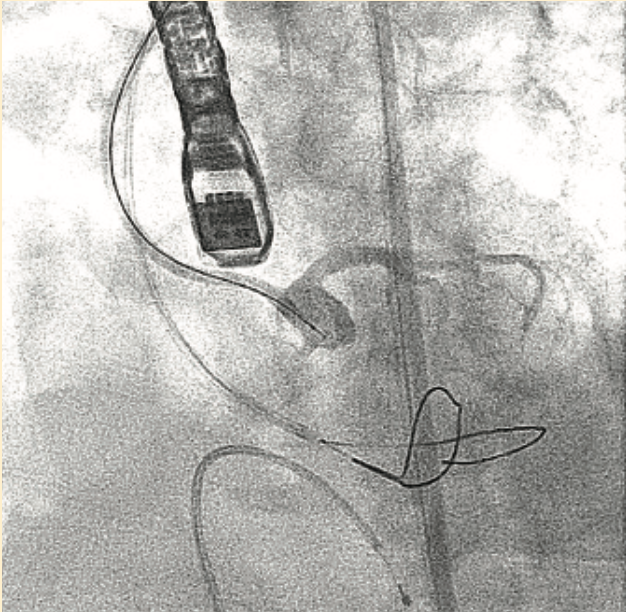

We planned to use cerebral protection during the case upfront, but the patient was known to have anomalous origin of her bilateral carotid arteries off of a single branch from the aortic arch, separate from the right brachiocephalic, and an anomalous insertion of the brachicephalic to the distal arch (Figure 2). We performed an aortic arch angiogram using a 15 cc contrast injection through a 5 French (Fr) pigtail with the ACIST CVi system (ACIST Medical) (Figure 3, Video 1) to guide the cerebral protection device from the anomalous brachiocephalic to protect the carotids. We proceeded with laceration of the left coronary cusp aortic valve leaflet. Aortic root angiography was performed using the same 5 Fr pigtail and a 10 cc contrast injection (Figure 4), then coronary angiography to identify the left coronary cusp (Figure 5). The optimal alignment of the left coronary cusp was determined by using a 6 Fr Amplatz left (AL) 1 guide catheter and a 6 cc injection with a lower pressure injection (Figure 6, Video 2). Finally, after the laceration was completed and the valve deployed (using small test injections from the ACIST contrast injector) (Figure 7, Video 3), we performed peripheral angiography with the 5 Fr pigtail advanced from the contralateral iliac artery to ensure adequate hemostasis of the large 14 Fr sheath access site (Figure 8, Video 4).